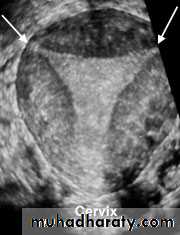

• Uterus

• Reconstructed coronal view of the uterus demonstrating cornuas (arrow) and cervix, with a normal uterine contour• Normal Uterus

• Planar views of normal uterus using volume contast imagingNormal Uterus